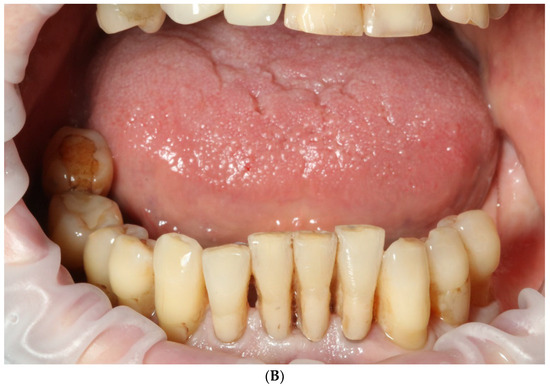

2.1. Patient Information and Clinical Findings